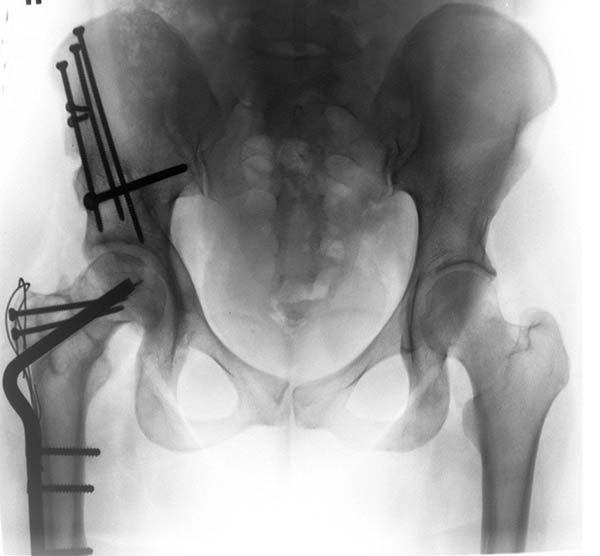

Больной, 24 года, спортсмен - борец вольного стиля, рост 170см, вес 92кг. Со слов была травма в детстве, но характер травмы описывает смутно и мед. документацию не предоставляет. Жалобы на периодические боли в области т/б сустава, но больше смущает укорочение конечности и хромота. Похоже на последствия остеохондропатии головки бедренной кости (Легга-Кальве-Пертеса) или неправильно консолидированного перелома. Объем движений в т/б суставе в пределах нормы, но по сравнению со здоровой ограничено: внутренняя ротация на 15гр., отведение до 25-30гр., наружняя ротация, сгибание, разгибание и приведение одинаково. Укорочение конечности 4.5см. Отмечается незначительная гипотрофия мышц бедра и голени: бедро в объеме меньше здорового на 5см, голень на 3см. Опыта ТЭТС при данной патологии у нас нет. Хотим отправить пациента за пределы республики. Больной к оперативному лечению морально и материально подготовлен)) При необходимости можно оформить квоту на ТЭТС.

Здесь комбинированная патология тазобедреннего сустава, связанная с высокостоящим вертелом и отсутствием (ротирована?) шейкой. А на стороне вертлужной впадины диспластический сустав. Обычно высоко расположенный вертел приводит к уменьшению силы мышц абдукторов, но отстутствие шейки привело к вертикальному расположению сил в суставе. Боли появляются из-за вертикального давления, а неровные контуры головки приводят к ограничению движений в суставе. Такое состояние быстро изнашивает сустав, и больные в молодом возрасте заканчивают тотальным протезированием.

Представленный случай имеет схожесть...., и последний снимок после 2 х лет.

Снимок выполнен в прямой проекции с внутренней ротацией. На днях сделаем СКТ с 3D модуляцией.

Описался: рентгеновский снимок выполнен в прямой проекции с наружной ротацией.